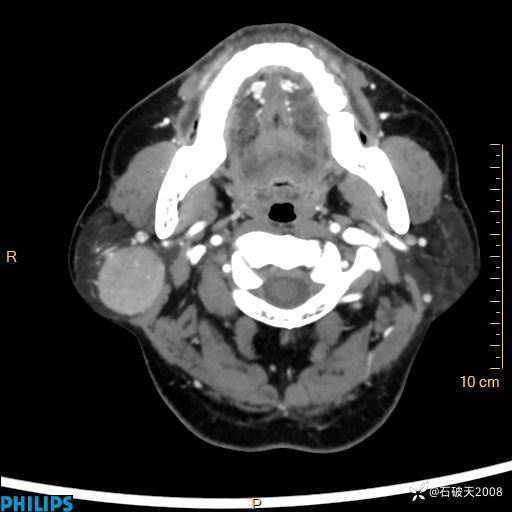

病例分享:颈部占位,一周后公布病理

男 57岁 主 诉:发现右侧颌下肿物1月余。

现病史:1月余前家属发现右侧颌下肿物。局部皮肤无红肿、热痛,无吞咽困难,无异物感,无恶心、呕吐,无头痛、头晕,无胸闷、胸痛,无发热、咳嗽、咳痰及呼吸困难。于我院行体表肿块彩超检查(2024.03.15我院)示:右侧耳下皮下软组织内低回声,未治疗。今为进一步治疗门诊以“腮腺肿瘤”为诊断收住我科,发病来患者神志清,精神可,饮食、睡眠及大小便正常,体重无明显下降。

MIP